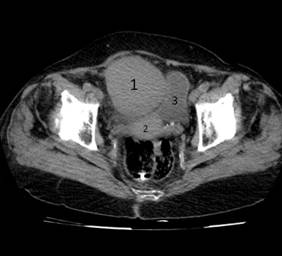

- Tomografía axial computadorizada (TAC) abdominal con doble contraste: en cortes a 5 mm se observó una masa tumoral a nivel de la fosa iliaca derecha que mide 89 x 78 mm, con densidades variables a predominio de las del rango de 50 a 70 UH y en el centro de 21 a 32 UH (imagen 1). La lesión captó el contraste intensamente. Comprimía y desplazaba el colon hacia arriba y a la izquierda, también, a la vejiga. Teniendo en cuenta las características de la lesión, se considera que se trata de un tumor sólido del ovario derecho.

IMAGEN 1. En las tomografías realizadas, tanto simple (izquierda) como contrastada (derecha), es posible observar la gran masa tumoral (1), que desplaza al útero (2) y a la vejiga (3)